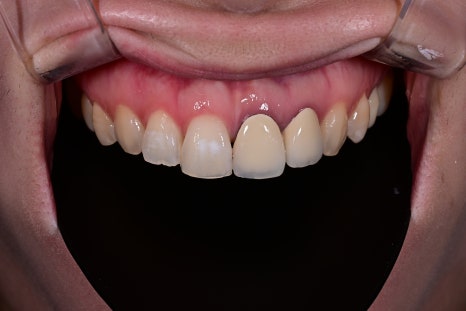

The patient first mentioned the naturalness of the color.

The existing crown had a noticeable brightness difference compared with the surrounding teeth,

which she described as looking like an “overlay,”

but the newly designed OBZERO looked natural even without makeup,

and she said it felt like her own teeth.

In addition, the incisal edge gained natural translucency and volume,

and the harmony with the lip line when smiling improved significantly.

She also said it looked more natural in photos.